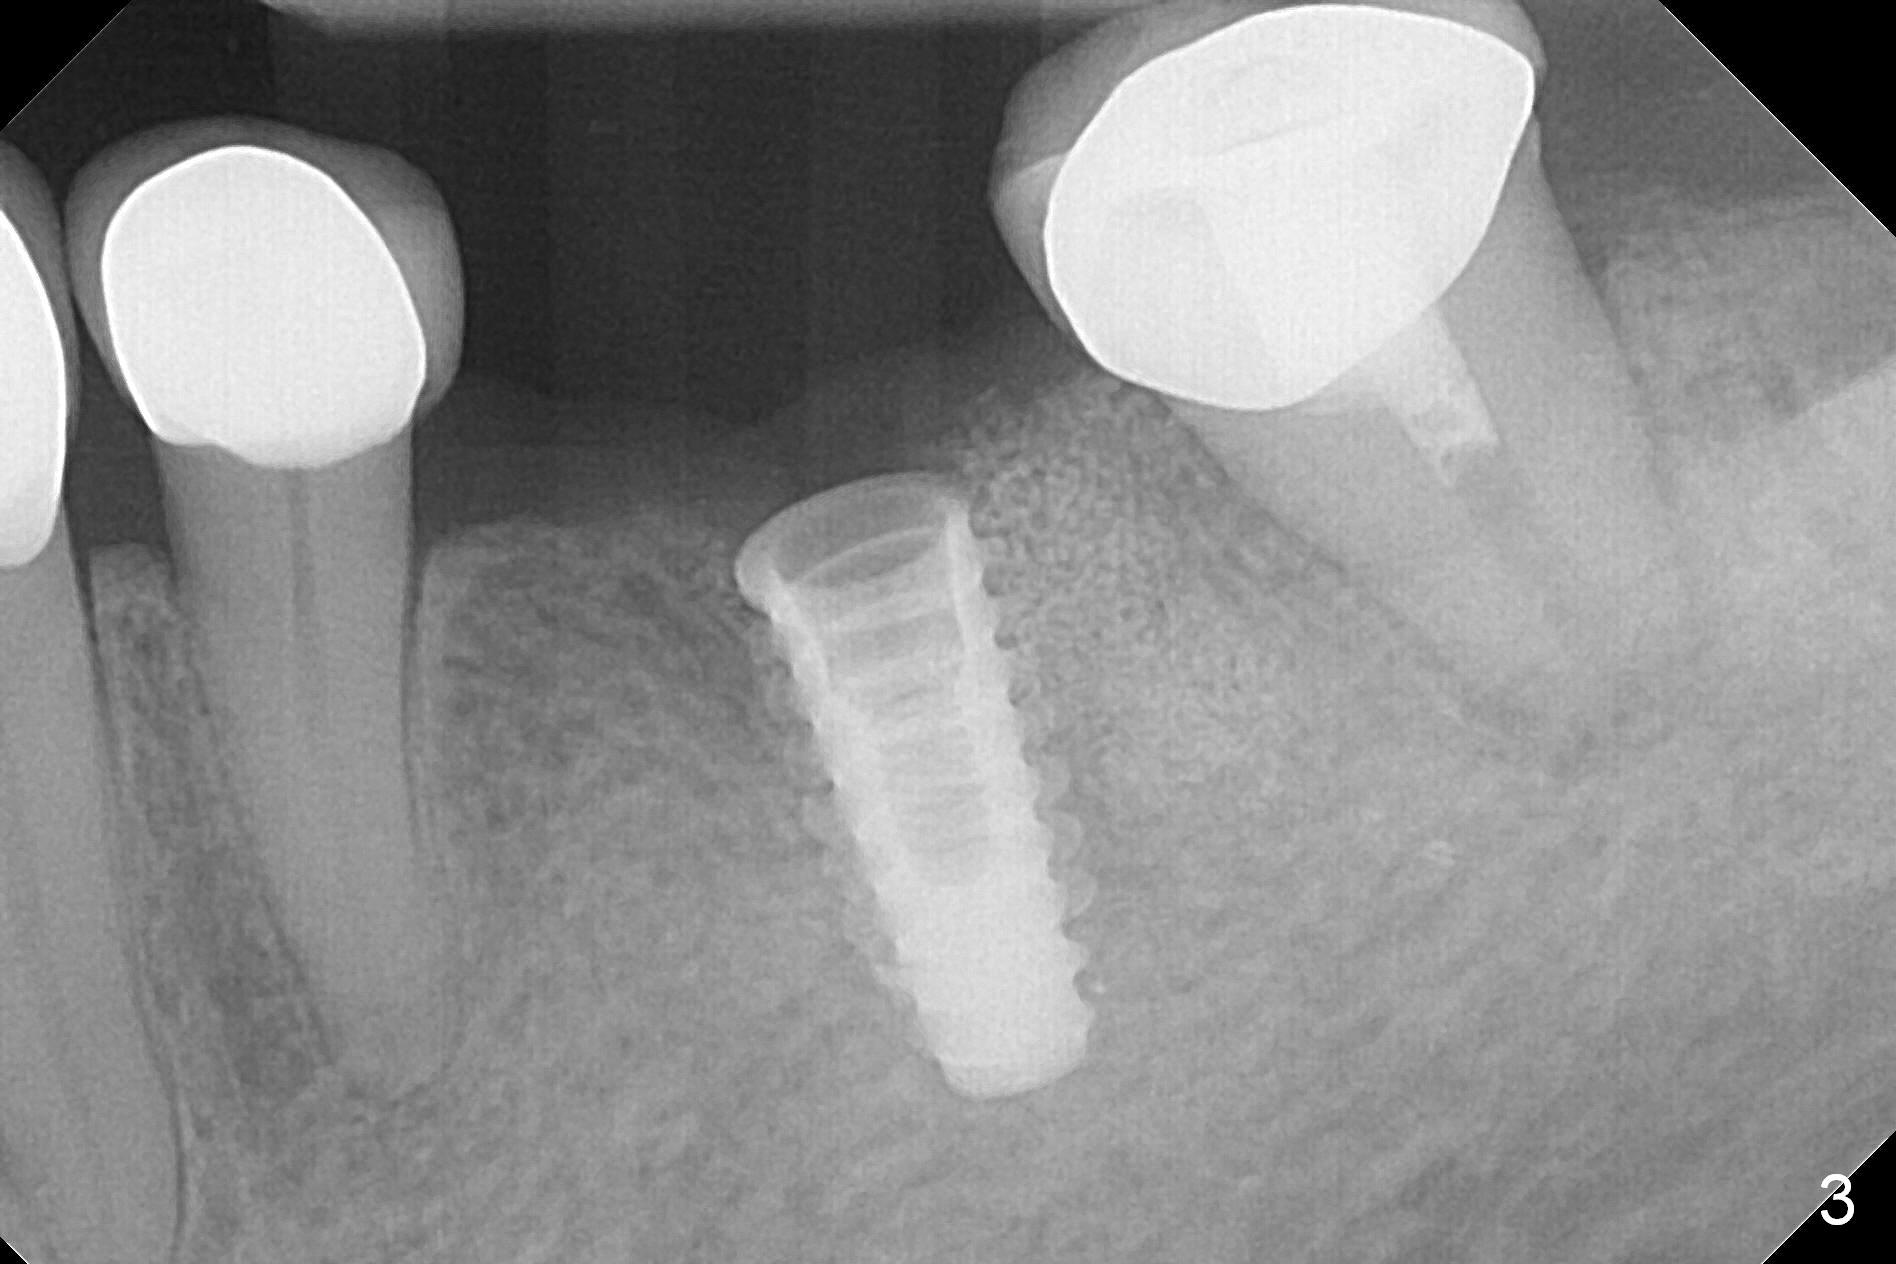

After making a 10 mm incision at the site of #19, #15c blade is used as an osteotome to start bone expansion, followed by Magic Split and Magic Expander (ME, 3 mm in diameter).  The depth is approximately the bottom of the mesial socket.  The osteotomy beyond the socket has to be done with 1.6 mm pilot drill (Fig.1) in combination of ME.  Following ME 4.3 mm and Magic Drill (MD) 3.8 mm for 15 mm (gingival level), a 4.5x11 mm dummy implant is placed with 50 Ncm (Fig.3); the implant looks narrow for the edentulous space.  After ME 4.8, MD 4.3 for 13 mm and Final Drill for 15 mm, a 5x11 mm IBS is inserted with >50 Ncm (Fig.3).  With 2 more turns of the implant, a 6.5x4(2) mm abutment is placed (Fig.4).  Periodontal dressing is applied around the abutment for additional retention.  A provisional is fabricated 3 weeks postop.  The provisional and abutment are loose 4 months postop (Fig.5).  After retightening the abutment, impression is taken for final restoration.  There is no bone loss 1 year 3 months post cementation (Fig.6).  After use of #100 file (Fig.7), the canal is debrided with #140 file with 1.5 mm shorter in working length with placement of Calcium Hydroxide paste.  Pain gets worse post RCT retreatment. There is limited native bone for primary stability when an immediate implant is placed (red dashed line: the superior border of the Inferior Alveolar Canal).  Prepare IS regular and extra wide kits and tissue-level implants (>5 mm).  Socket preservation may be done instead.  If the socket is large and the vein is not so small, prepare PRF.  In fact blood drawing fails.  When the tooth is extracted, it is sensitive to remove granulation tissue.  Socket preservation is done with Vanilla graft at #18 (Fig.8); there is ~3.5 mm bone between the bottom of the single socket and the Inferior Alveolar Canal (red dashed line).  The socket at #18 seems to have healed 4 months post extraction (Fig.19), but the bone height appears to have been reduced (compare Fig.10,11).  The buccolingual width is also decreased (Fig.12,13).  A 4.5 or 5.0x10 mm implant is appropriate for the site (Fig.14).  There is no bone loss at #19 (which may be associated with the bone expansion) 1.5 years post cementation (Fig.15).  Therefore the osteotomy at #18 will be assisted with bone expanders after 2.2 mm drill.